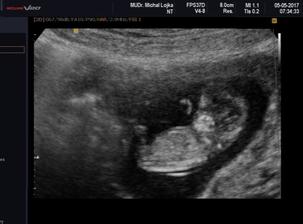

@verryk dekuji moc. Dnes byla kontrola a vse v poradku. Mi i je o 3 dny napred tedy 11+0 a mela sem byt 11+4